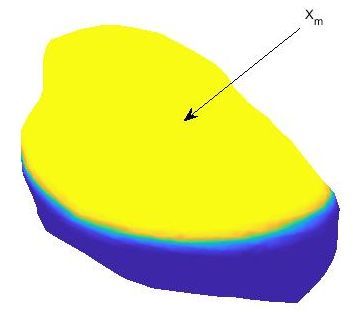

We have applied our proposed procedure to the solution of equations (40)-(42) with the parameters shown in Table 2. These equations are solved on the epicardium, which is the outermost surface membrane of the heart and which is shown in Figure 7(a). We also show the points used for the numerical solution of the problem. These points have been obtained from a computerized tomography (CT) of a real patient [8]. Therefore, it is a realistic model in which we do not have information neither on the normal vectors nor on the curvature of the surface. We consider

| (43) |

shown in Figure 7(b). Here, denotes the Heavisade function, the time when the stimulus ends, the position where the stimulus is applied, and its spatial width.

We use the same method that in the previous example for temporal integration. The solution shows the propagation of the electric excitation along the membrane. For instance, Figure 7 (c) shows the transmembrane current 50 ms after the stimulus ends. The tissue goes from a resting to an excited state. Finally, the membrane returns to the resting state awaiting for the next stimulus. This behavior can be observed in Figure 7 (d), where we show the evolution with time of the transmembrane voltage and the gate variable at the point in Figure 7 (c). As we can see, the cardiac tissue experiences the different stages of a heartbeat corresponding to those shown in [25].